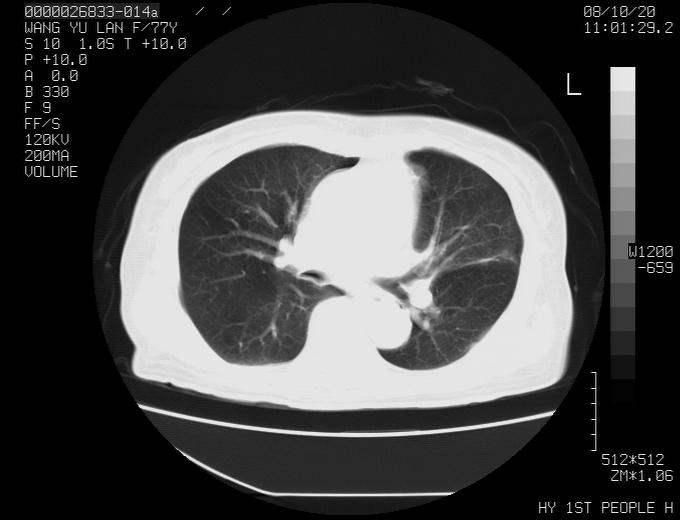

女性,77岁,胸部疼痛半月。左上肺团块影,本人考虑血管畸形,请分析

非常典型的avm(谢谢楼主,收藏了)

左上叶前段多发结节肿块并前段支气管息肉样结节、上叶腋亚段阻塞性肺炎,以结核可能性大。

纵隔有多个淋巴结肿大,提示周围型肺癌并转移可能性大。

1、考虑avm可能性大。2、纵隔有肿大淋巴结,左肺上叶有炎性病变,不排除肺癌并转移可能。